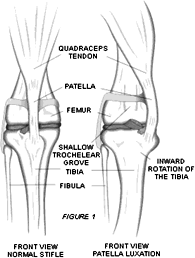

- luxatie naar mediaal, dwz naar de binnenzijde van de knie, dit is de meest voorkomende vorm van luxatie. We zien deze frequent bij katten en dan nog meer speciaal bij raskatten (zie fig.1).

fig 1. normale knie en knie met patella luxatie |

Het kniegewricht is het scharnier tussen de femur (dijbeen) en de tibia (onderbeen). Aan de voorzijde van de femur loopt een sleuf waar de knieschijf overheen glijdt. Boven zit de knieschijf vast aan de pees van de Quadriceps-spier en aan de onderzijde zit de kniepees die op haar beurt weer vastzit aan een beenkam van het onderbeen.